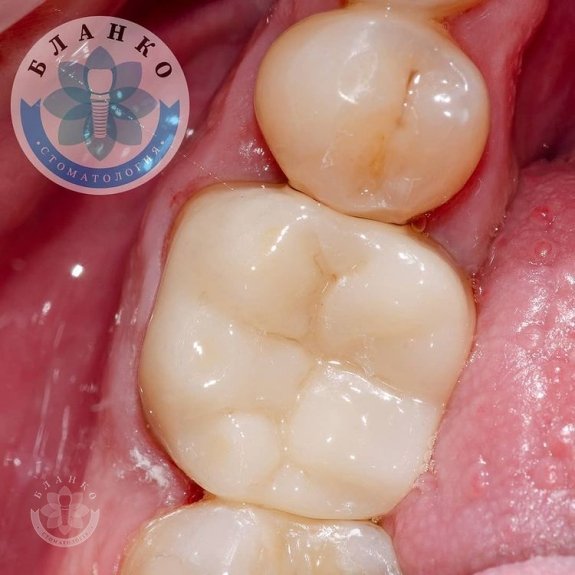

✳️На начальном снимке мы видим зуб 4.6 ( обведен красным цветом ),в котором наблюдается хроническое воспаление вокруг корней зуба и плохая реставрация из пломбировочного материала, которая давно отошла от тканей зуба и под которой развился вторичный кариес ( снимок №2 ).

— сняты оттиски и изготовлена высокопрочная, гипоаллергенная и высокоэстетичная коронка из диоксида циркония.